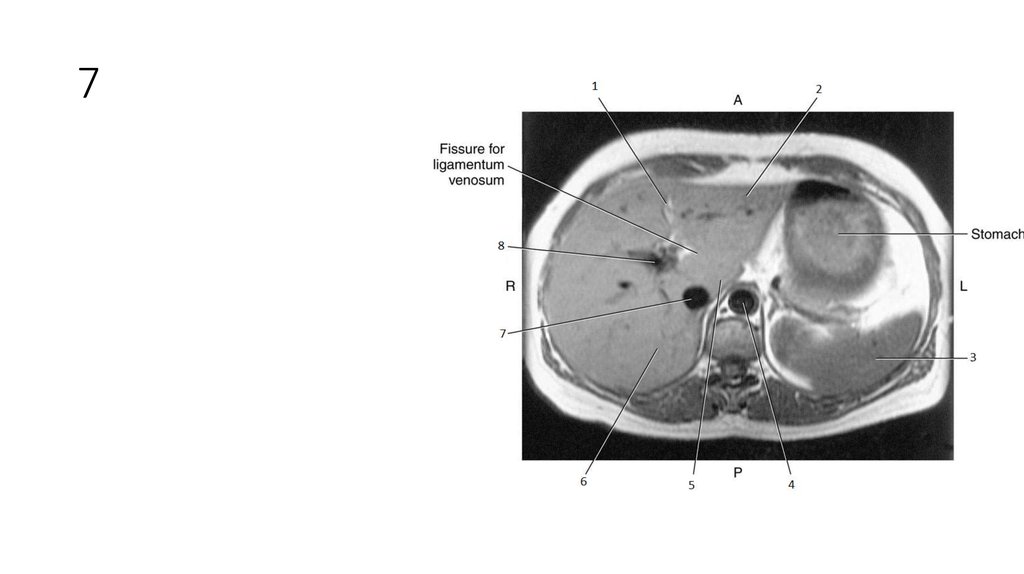

16. 1

17. 1

• Falciform Ligament

18. 2

19. 2

• Left lobe of Liver

20. 3

21. 3

• Spleen

22. 4

23. 4

• Aorta

24. 5

25. 5

• Caudate Lobe of Liver

26. 6

27. 6

• Right Lobe of Liver

28. 7

29. 7

• Inferior Vena Cava (IVC)

30. 8

31. 8

• Portal Vein